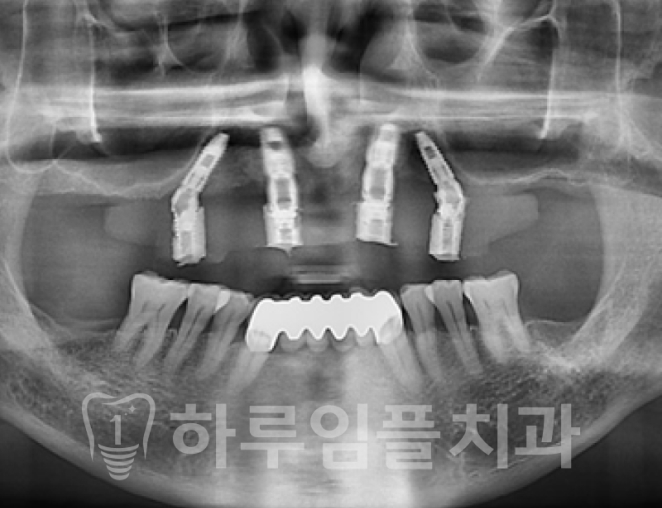

컴퓨터 분석을 통해 임플란트를 심을

위치를 선정하고 식립을 진행했습니다.

임플란트의 모양이

일반적인 경우와 좀 다르죠?

4개의 치아로 전체 치아에 해당하는

보철물을 지탱해야 하기 때문에

지지력이 중요합니다.

그래서 뒤쪽의 임플란트 각도를 줘서

심게 됩니다.